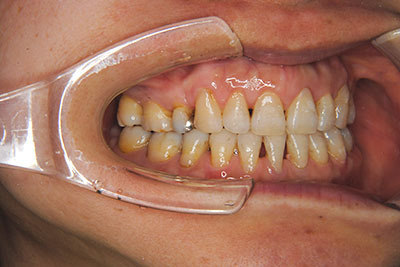

おとなの方でも矯正治療をあきらめないでください!

いくら歯が動き易くとも、本人がやる気でなければ効果は出ませんし、むし歯発生のリスクも高まります。おとなの方は顎の成長が終わっているため、治療の計画が立てやすいとも言えます。「もう大人だから…」とあきらめず、一度ご相談ください。